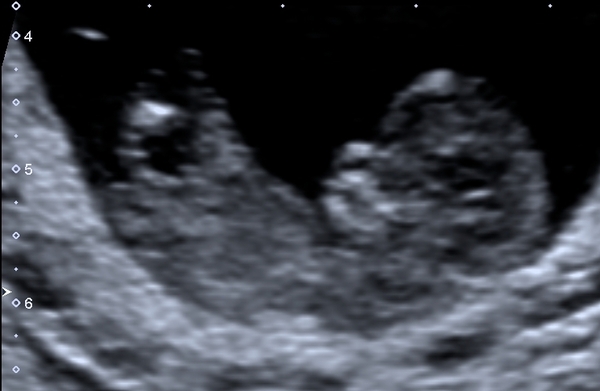

@Murderino haha know that feeling. For a few reasons I don't personally agree with extra scans from private companies for non medical reasons so 12 week dating scan was first time seeing baby and it was the longest wait ever.

I was more nervous than I imagined considering I've been through this twice before

But was so worth the wait.